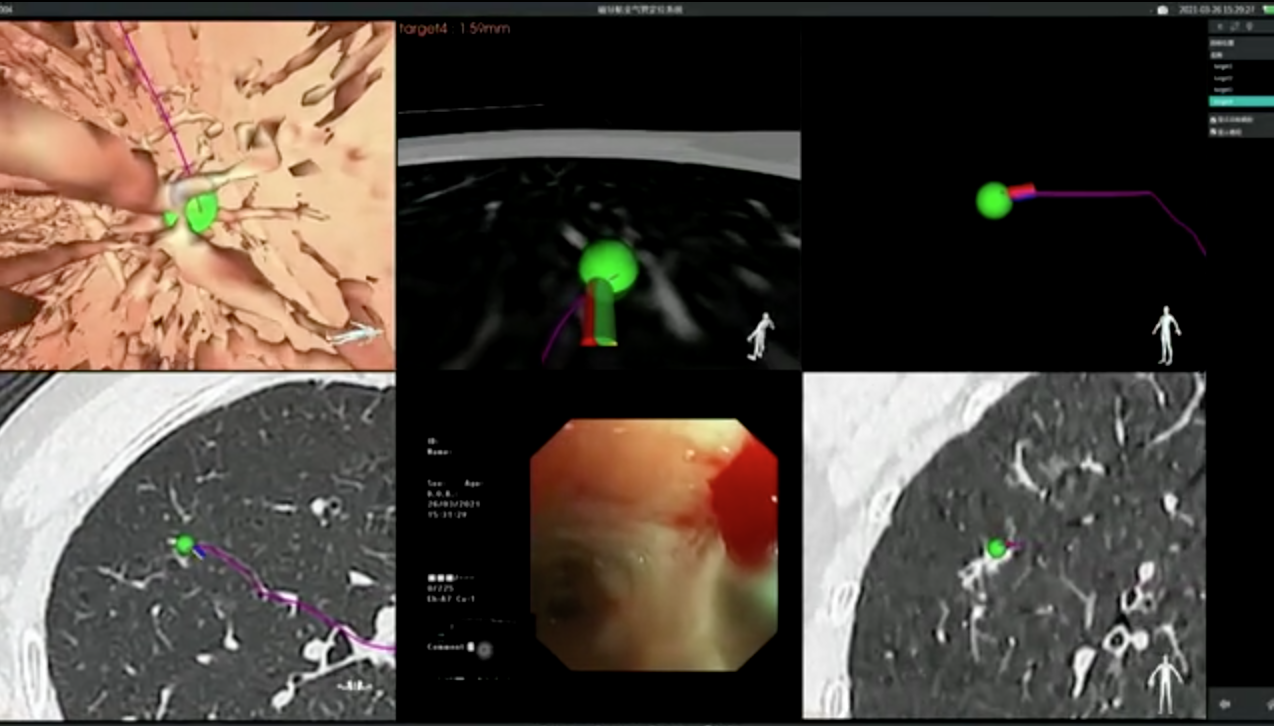

3月26日,由呼吸与危重症医学科蒋军红主任带领介入与血管外科团队对这位患者进行了磁导航支气管镜检查,顺利完成标本取样,并在术中对病灶进行了精准消融。术后,病理提示为原位腺癌。磁导航支气管镜检查精准定位,大大提高了诊断率,同时最大限度保留肺部功能,提高了患者的生活质量。

电磁导航支气管镜是一种以电磁定位技术为基础,结合计算机虚拟支气管镜与高分辨率螺旋CT的特点,经支气管镜诊断的新技术。通俗理解就是我们肺部的支气管像道路一样错综复杂,而肺部的一些病变如结核及肿瘤等病灶是我们想要到达的目的地。磁导航就如同星导航系统,可以给我们选择快捷而准确的线路指引我们到达目的地。